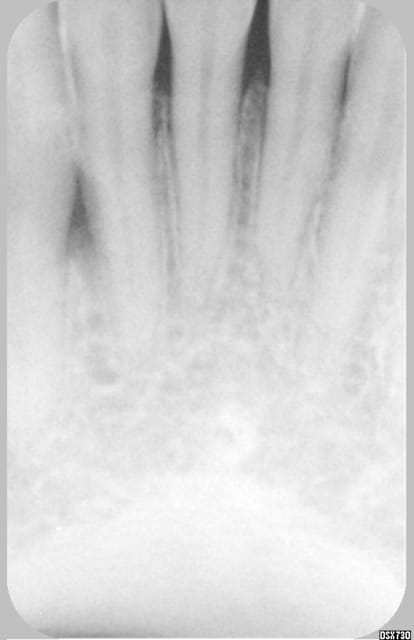

Patiente la cinquantaine, venue avec abcès en vestibulaire entre 33 et 32.

Lors du 2° rdv, plus de douleur, test au froid positif sur 33, 32, 31. Pas de réaction exploitable au chaud. Percution à peine plus sensible sur 32. Sondage normal autour des dents.

L'image montre une raréfaction osseuse entre 33 et 32.

j'ai plusieurs idées, mais j'aimerai votre (vos) avis. Merci

Si on arrive a éliminer le diag. de fracture, félure (petite diagonale radio+ sur 32 , artefact?), je rejoins BX pour poche paro entre 33 et 32.

t'as pas une radio plus precise de l'espace interdentaire ,une photo de bouche? les sepas des autres dents me paraissent un peu douteux tout de même .

ce n'est pas un vrai problème paro car le septum n'est pas touché au collet . les félures donnent il me semble une image différente.

c dingue, on dirait vraiment une lésion d'origine endo.....mais le test au froid est positif.....ceci dit le test au froid est il fiable à 100% ?? je ne crois pas.....il faudrait confirmer la vitalité pulpaire par un test électrique, voir un test du fraisage....

Une idée bête : 33 faussement réactive au test au froid, en fait nécrosée ou pulpe partiellement nécrosée (je n'ai connu cela que sur les pluriradiculées mais bon) avec lésion apicale (mouais) remontant en mésial ?

33 biradiculée (j'ai l'impression de voir quelque chose superposé à la racine, mais ce doit être la fatigue) avec 1 canal nécrosé ?